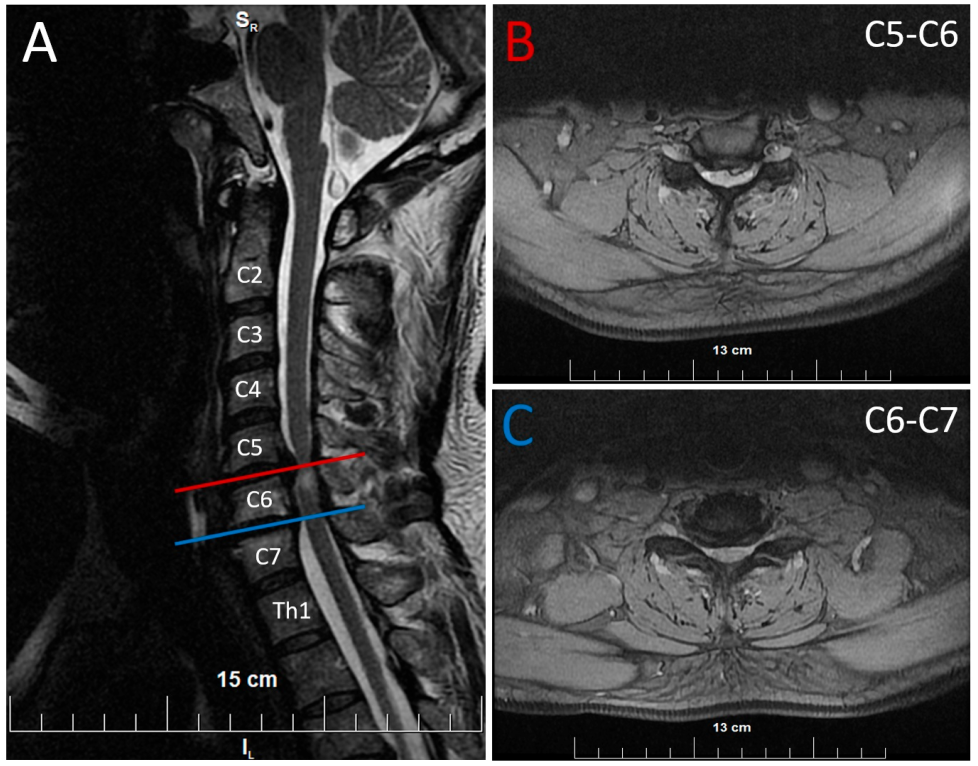

2. Case Presentation